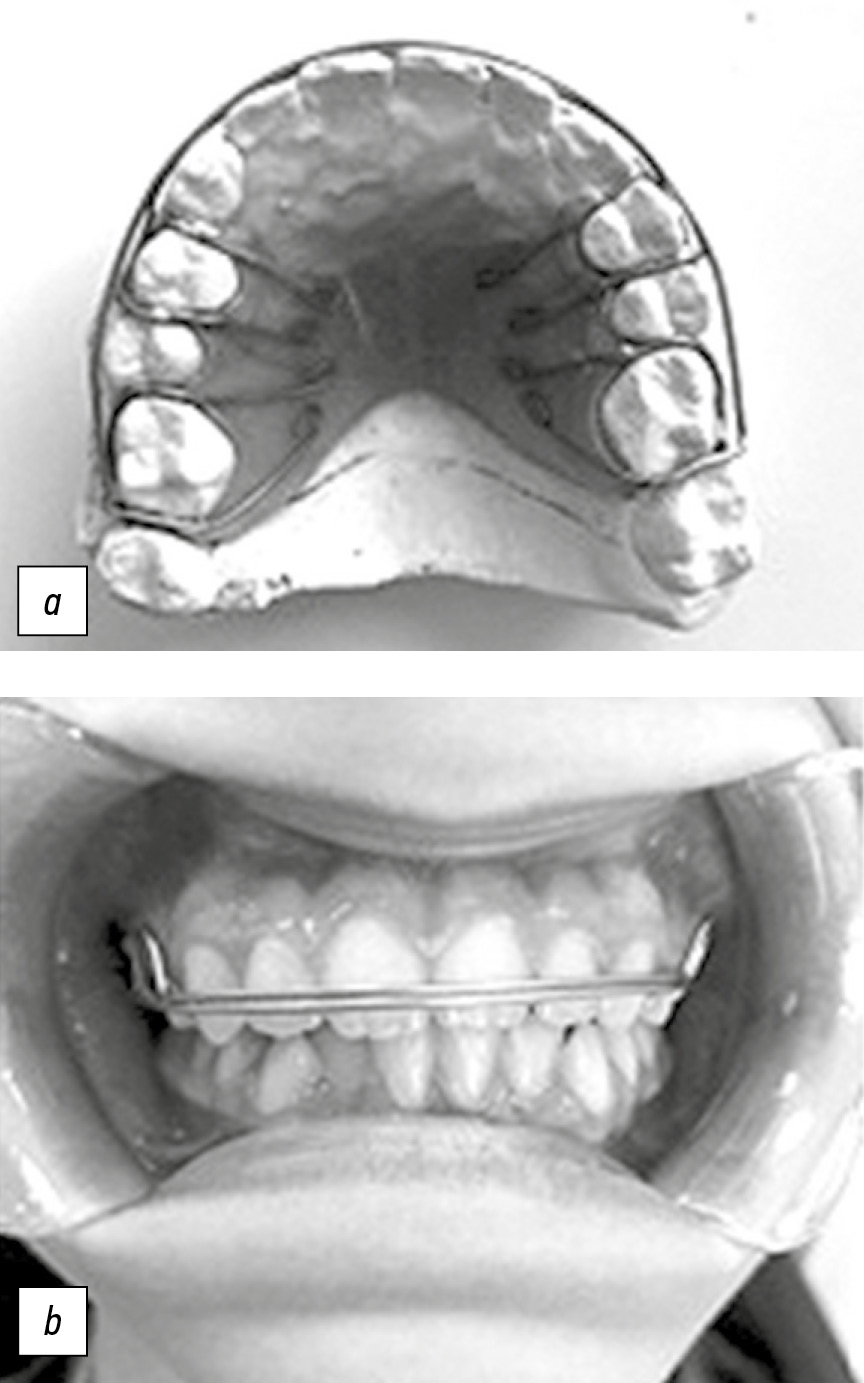

Функцию ретенционного аппарата у пациентов с сочетанной патологией окклюзии зубных рядов выполняли съемный ретенционный аппарат Hawley (рис. 1) и съемный ретейнер собственной конструкции [№ государственной регистрации 2018107373/14(011304) от 27.02.2018 г., авторы Водолацкий В.М., Макатов Р.С.] (рис. 2).

Рис. 1. Ретенционный аппарат Hawley.

Fig. 1. Hawley retention device.

Рис. 2. Съемный ретейнер собственной конструкции (a) в полости рта (b).

Fig. 2. Removable retainer of own design (a) in the oral cavity (b).